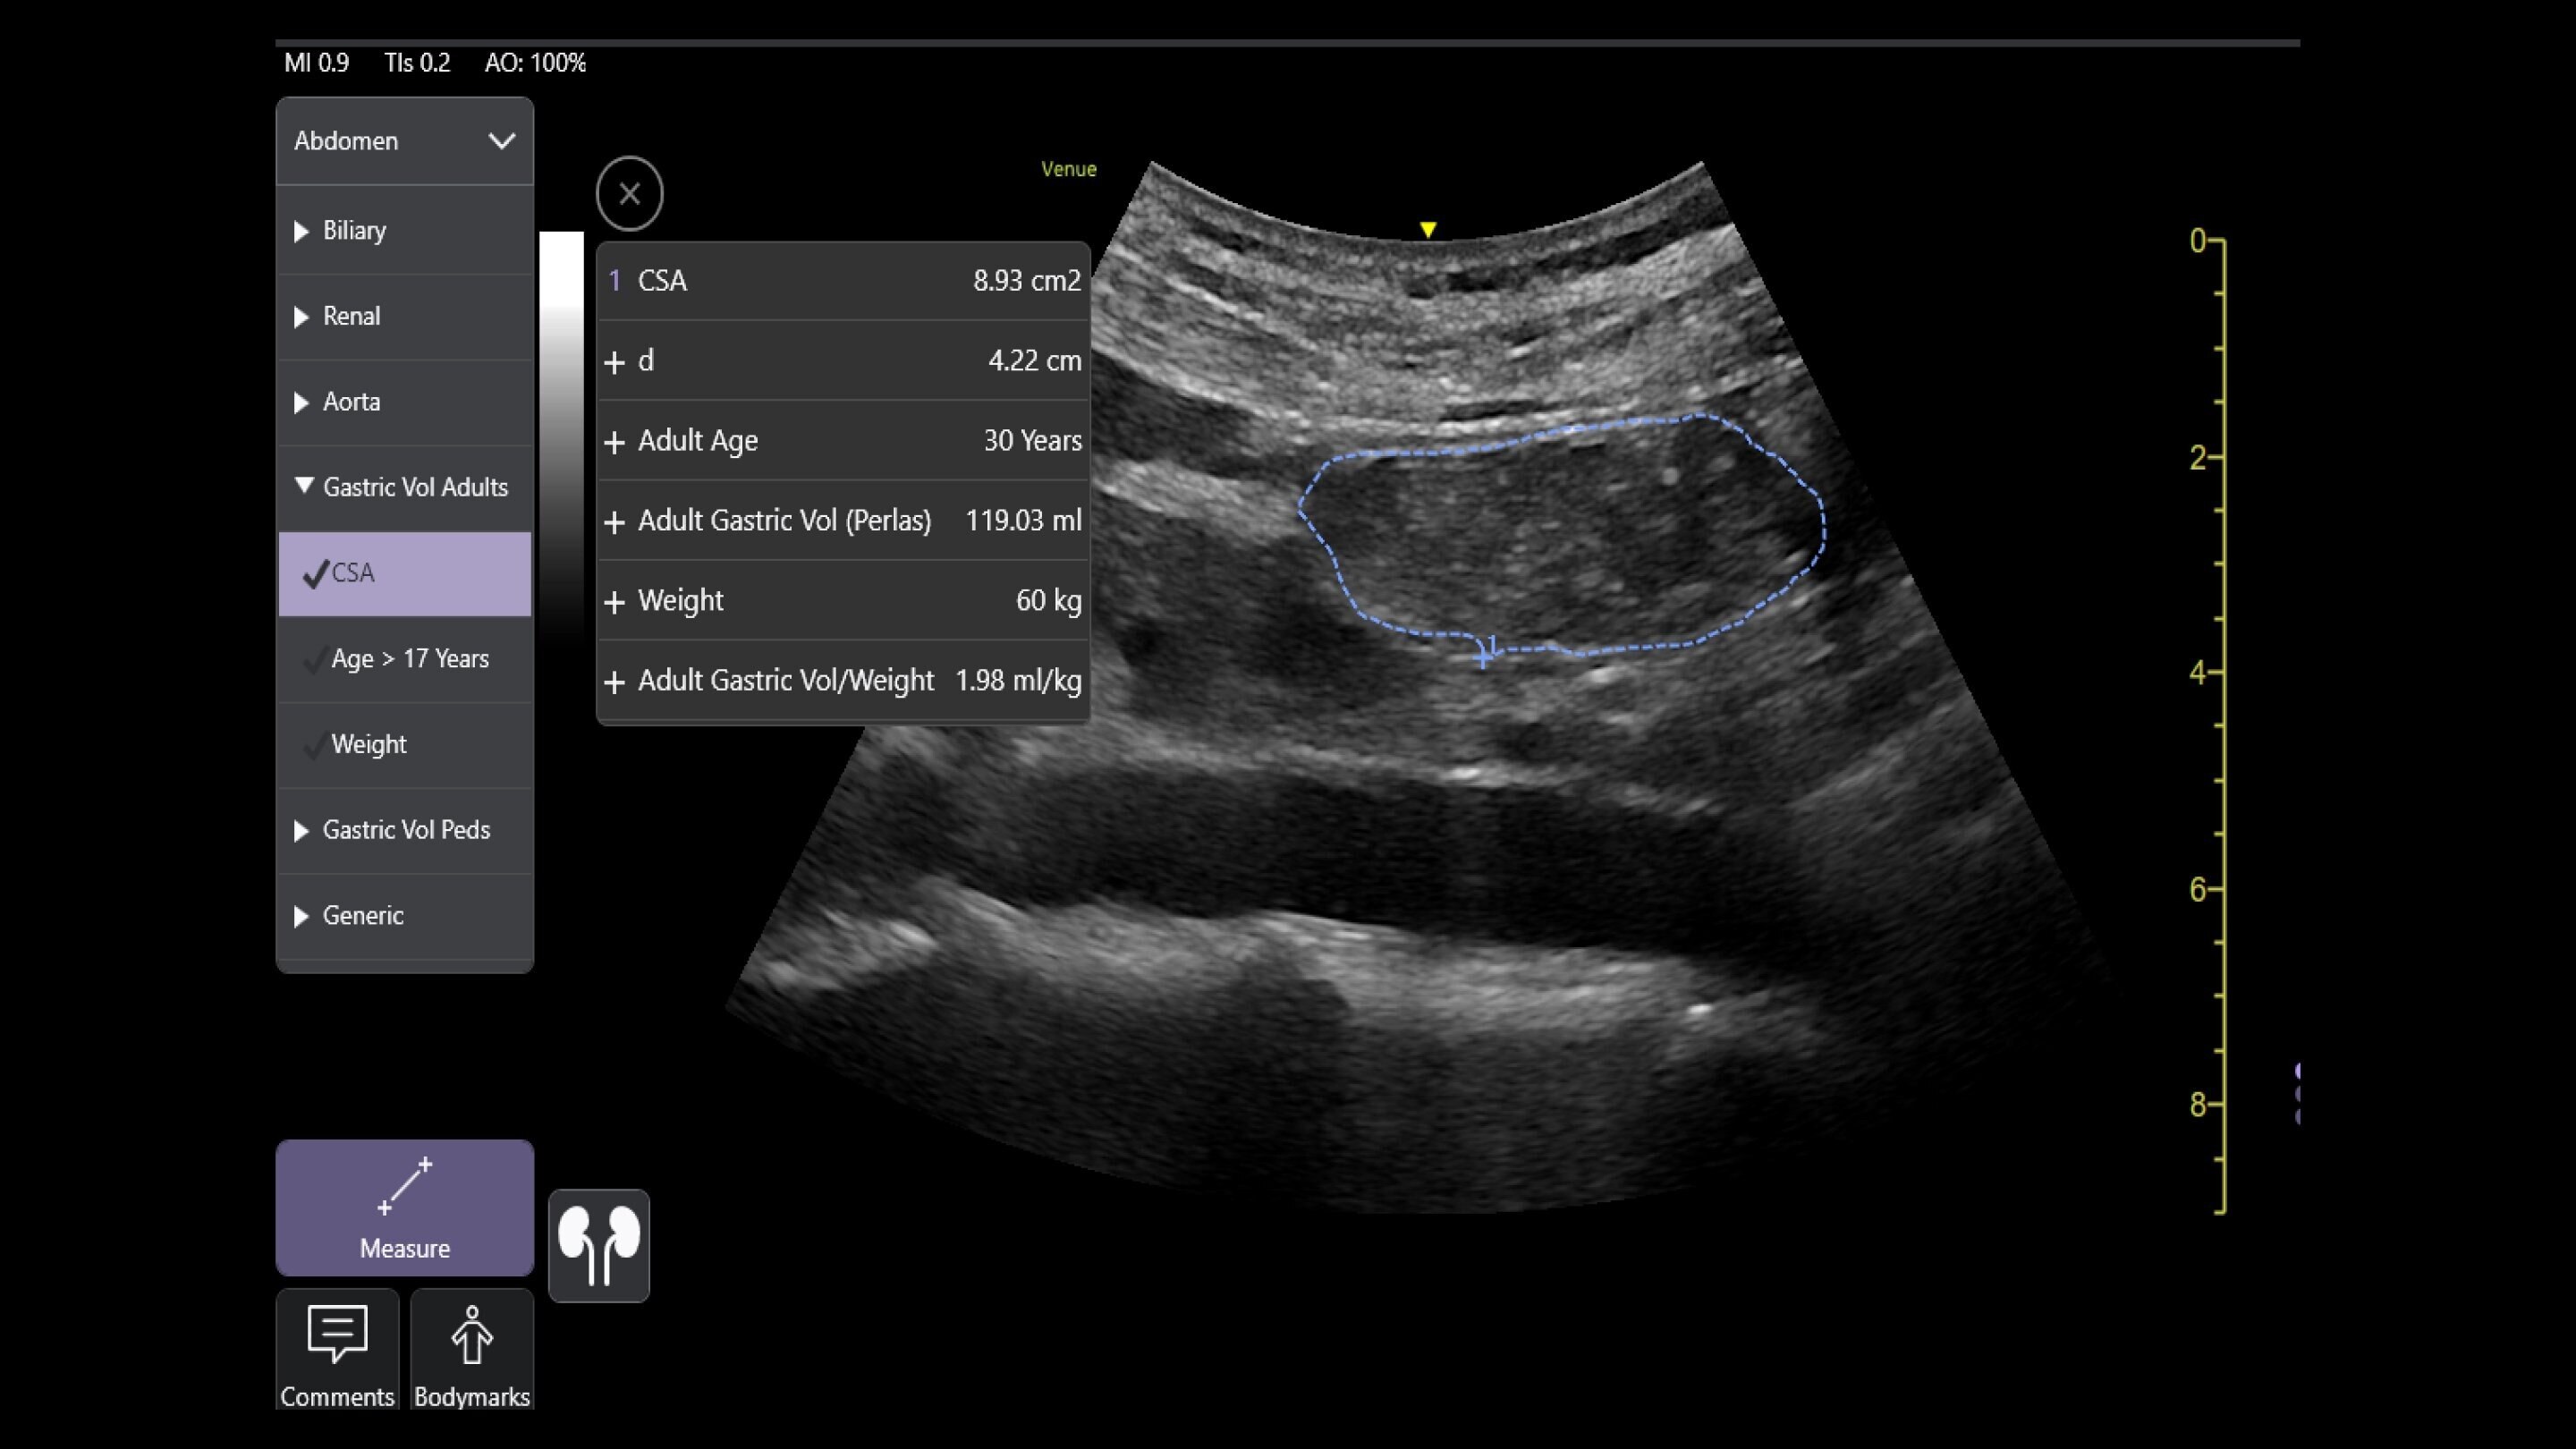

Venue Sprint™ gives you the uncompromised image quality and smart workflow of Venue™ family systems along with the freedom and maximum portability of wireless probes. This all-in-one, entry-level solution combines wireless connectivity with a small, streamlined console. It features Venue family software, to give you access to the AI tools you need, to simplify advanced exams whenever and wherever care is needed.

A curved array on one side and linear array on the other of the dual wireless probe enables clear assessment of deep and shallow anatomy without switching probes.